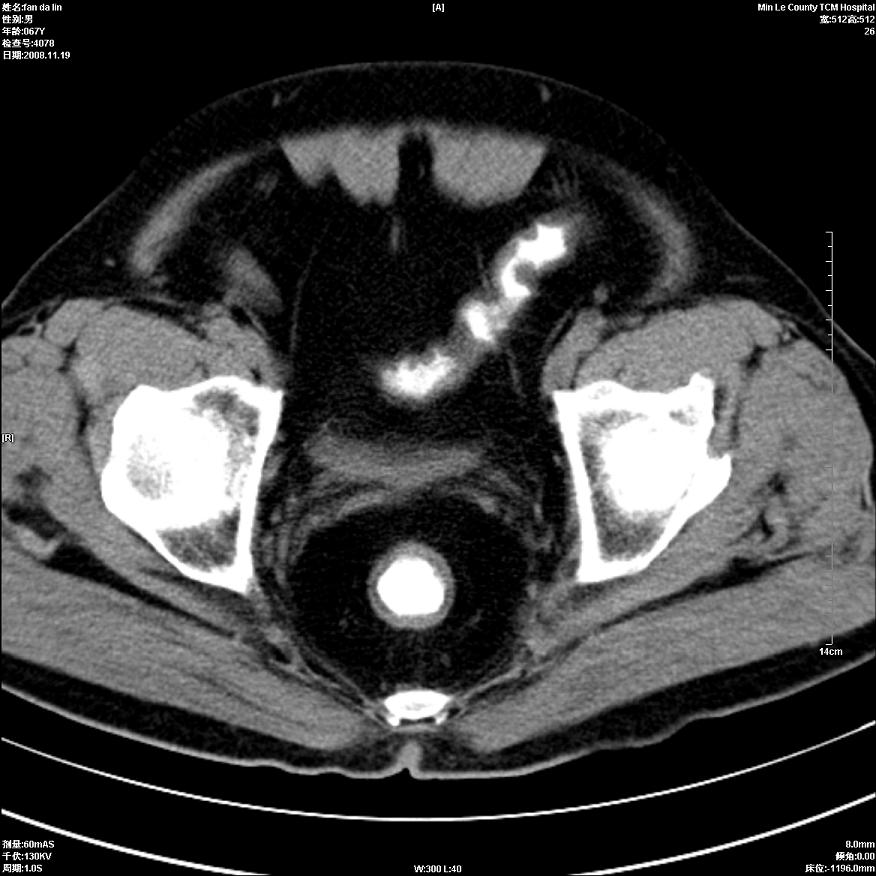

标题: CT16698:M67Y,看看直肠下端是不是病变 [打印本页]

标题: CT16698:M67Y,看看直肠下端是不是病变

粘膜皱壁,不除外内痔

直肠及乙状结肠管壁均增厚,考虑炎症.

直乙交界处肠壁不规则增厚,还是做个肠镜吧